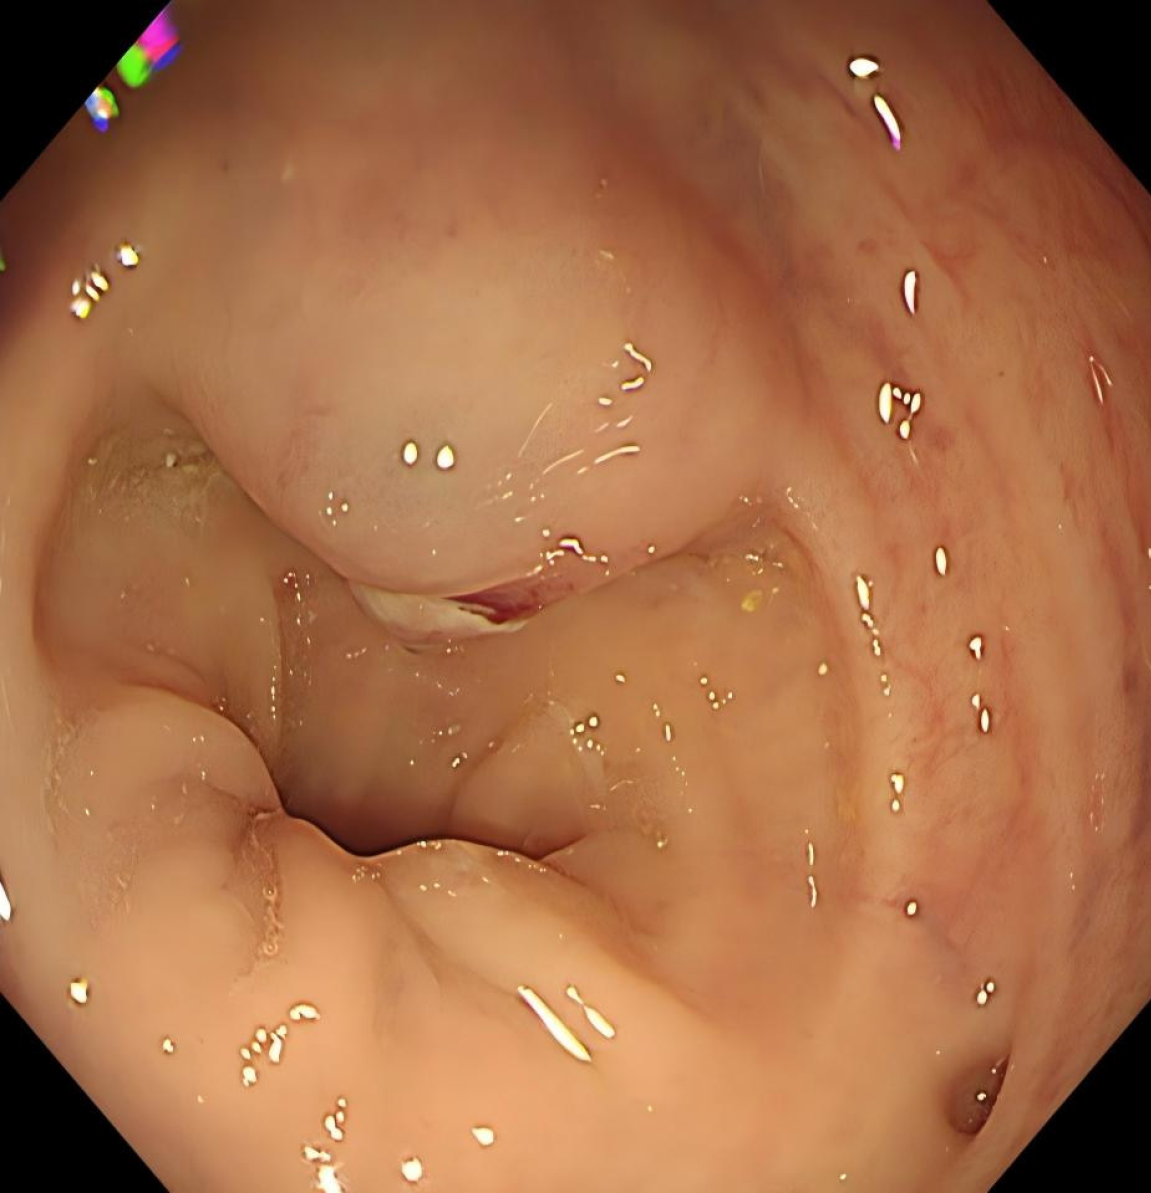

The patient was admitted to Union Hospital due to intermittent rectal bleeding. Colonoscopy revealed a 2.0 cm × 3.0 cm elevated lesion with surface ulceration located 10 cm from the anal verge (Figure 1). Endoscopic ultrasound demonstrated poor delineation of the mucosal and muscularis propria layers, appearing as a mixed echogenic solid mass.